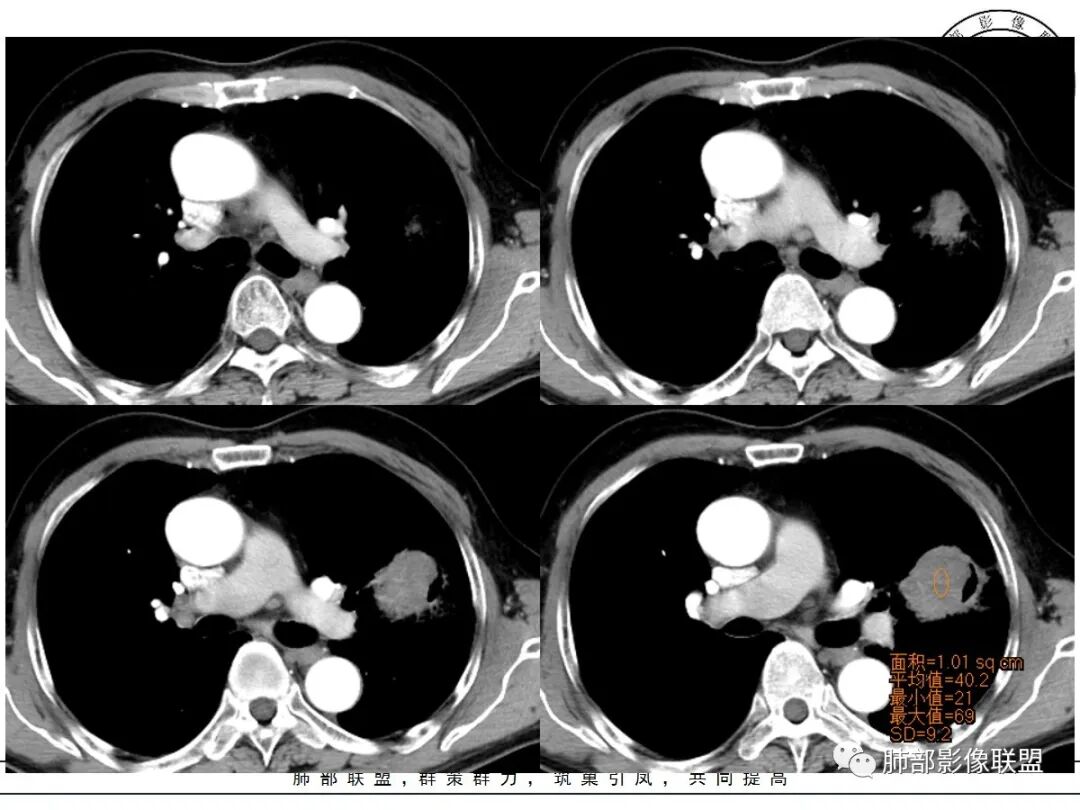

强化如何?

生来征服~浪子:

强化有疑问,前面感觉有低密度的,有些图好像又均匀

小锁:

不均匀中度强化

尘缘:

不均匀轻中度渐进强化。

中远端堵塞,堵塞端圆钝

炎性? 肺炎型肺癌待排

这个空洞的性质很重要,对最后诊断结果影响大,如果中间没有曲菌球,那就是偏心空洞,指向恶性,如果是曲菌球引起的新月形改变,那就不一定。至于到底是曲菌球还是偏心空洞,需要仔细看看强化情况。

不均匀性强化,远端坏死比较明显

如果强化明确,那就可以排除曲菌球。